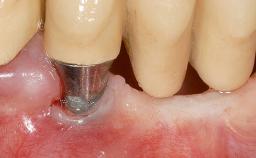

Soft-Tissue Volume Augmentation Using a Connective-Tissue Graft Harvested from the Maxillary Tuberosity

In 1983, a 51-year-old non-smoking patient was referred for the treatment of moderate chronic periodontitis. At the initial examination, 47% of sites exhibited probing depths of 4 to 6 mm. Periodontal therapy consisted of initial periodontal treatment including oral-hygiene instructions and supra- and subgingival debridement, followed by periodontal surgery to eliminate residual pockets.

| Soft Tissue Grafting | Simultaneous |